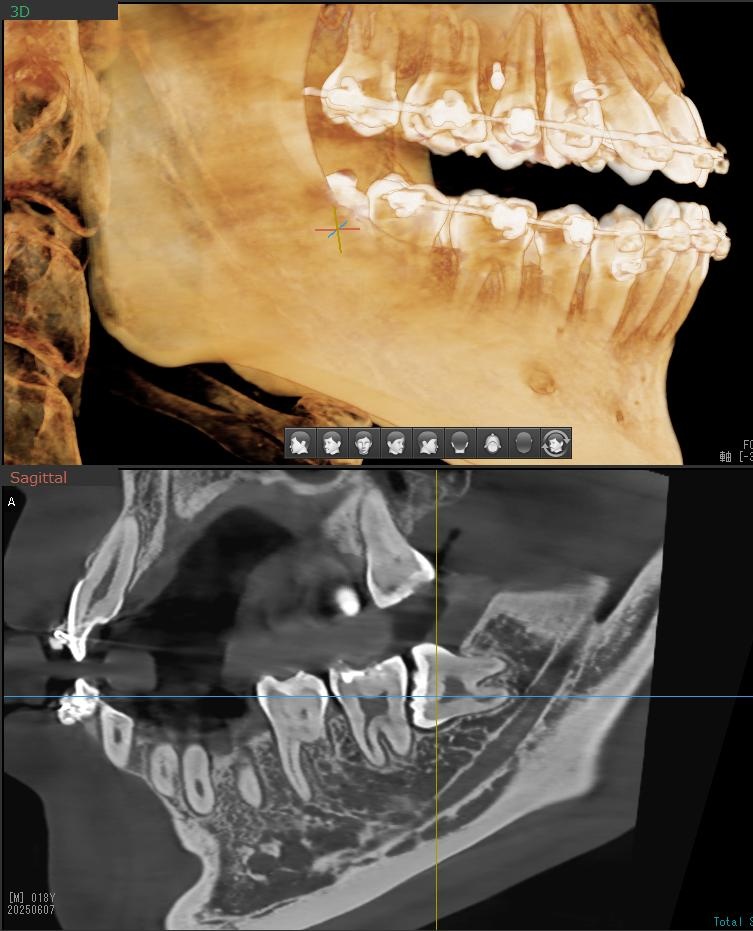

さらに、下顎の親知らずは下歯槽神経に非常に近いところに生えている場合もあるため、CTも撮影し詳しい解析を行います。

親知らずが生えている位置が、神経に近い、あるいは神経に当たっている場合は、大きな病院に紹介する場合もあります。

親知らずの根っこは下歯槽神経から近い距離にありますが、抜歯は可能との診断でした。